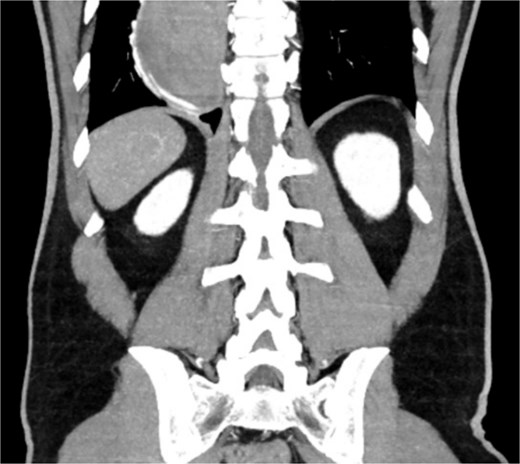

A 46-year-old male with a history of achalasia, for which he had undergone Heller myotomy with Nissen fundoplication in 2015, presented to the emergency department with a 2-day history of weakness and hematemesis. On admission, laboratory investigations revealed a significant drop in hemoglobin to 5 g/dl. Vital signs demonstrated tachycardia (122 beats per minute) and hypotension (70/50 mmHg), consistent with hemorrhagic shock. Initial management included aggressive resuscitation. Emergent gastroscopy was performed, which revealed the stomach filled with blood but failed to identify a clear bleeding source (Fig. 1). The patient remained hemodynamically unstable, necessitating transfusion of additional blood products. A computed tomography angiography was subsequently performed, revealing a markedly dilated, sigmoid-shaped esophagus, likely a sequela of end-stage achalasia. Furthermore, a contrast blush in the region of the distal esophagus, consistent with active ongoing bleeding (Fig. 2). An initial attempt was made to control the bleeding through angioembolization; however, this attempt was unsuccessful.

Demonstrates the gastroscopy findings, showing the stomach filled with blood.

CT scan showing a markedly dilated esophagus with contrast blush in the distal third.